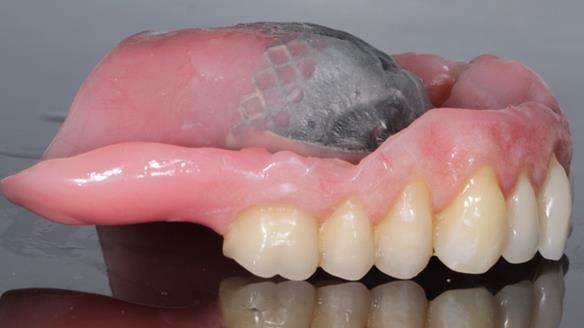

Welcome to Newsletter 62. In this edition, I walk through the process of removing 5 upper anterior teeth, adding to an existing upper RPD, followed by creating and fitting metal based complete dentures for Rafique, a 71 year old man.

The detailed clinical situation and treatment process are outlined below, with clinical work provided by me and technical work by Rowan Garstang. The treatment spanned 12 months, involving removing 5 upper anterior teeth, adding to an existing upper RPD, followed by creating and fitting metal based complete dentures.